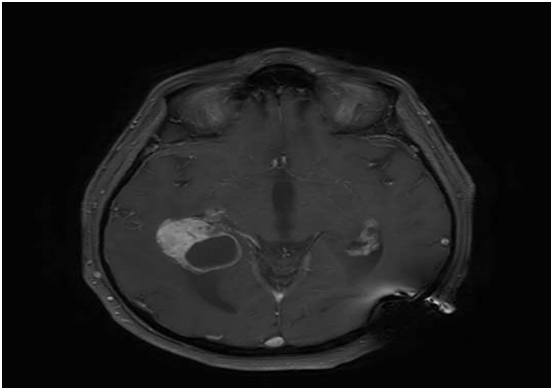

We report on an 72-year-old male patient with a history of treated RCC who presented after 40months with a classic but severe triad of Hakim and Adams (gait disturbance, urinary incontinence and cognitive dysfunction) due to hydrocephalus related to a choroid plexus mass in the trigonum of the both lateral ventricles (Figure 1). Because of the severity of symptoms we decided to first treat the symptoms of normal pressure hydrocephalus initially by external ventricle drainage and finally by VP-shunting to aim for fast symptomatic relieve. Follow-up imaging after 6weeks however showed clear disease progression unilateral in the right sided trigonum (Figure 2). Consequently the patient was referred to surgery to remove the right-sided lesion. The left-sided lesion was not resected. The histopathological examination was consisted with a RCC metastasis as the lesion had the characteristic clear-cell pattern immunoreactive to RCC and CD10 (Figure 3). The patient was referred to the medical oncologist for additional systemic treatment with tyrosine kinase inhibitors.

Figure 1 MRimage (T1 sequence) showing a bilateral (right >left) choroid plexus mass.